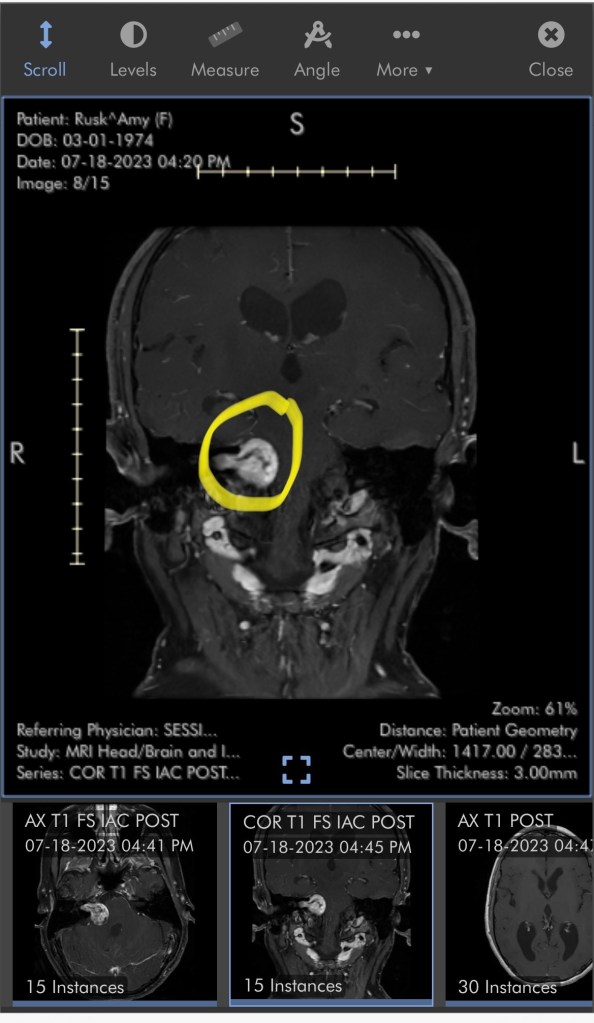

So now I have something called an acoustic neuroma – which is fancy for a non-cancerous tumor. Acoustic Neuroma info

That’s my head! I’ve been losing hearing in my right ear for about two years now. I had it checked over a year ago and we agreed to keep an eye on it. Life got in the way (don’t do that!!!) and I put off the recheck. They had me get an MRI and sure enough, there’s an intruder in there who will need to be evicted via surgery.

WHEN? When is your surgery? That has been the big question. I have to get a CT scan on Monday and then hopefully we’ll be able to kick this tumor out. She’s gotten quite comfortable in there, which makes the surgery pretty involved. They can’t preserve my hearing, but they have to be careful around those other nerves.